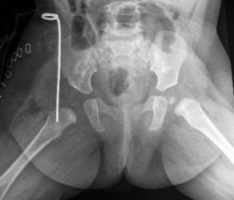

Рентгенограммы больной Т., 10 месяцев. Диагноз: врожденный вывих бедра справа.

3. Открытое вправление бедра в сочетании с подвздошной остеотомией таза по Salter и укорачивающей корригирующей (деторсионно-варизирующей) остеотомией бедра

В тех случаях, когда головка бедра смещена высоко относительно впадины, помимо собственного открытого вправления бедра возникает необходимость вмешательства как на тазовой, так и на бедренной кости - т.н. «классическая триада».

Операция применяется у детей от 2 до 6-7 лет и позволяет обеспечить хорошие отдаленные результаты лечения у большинства пациентов.